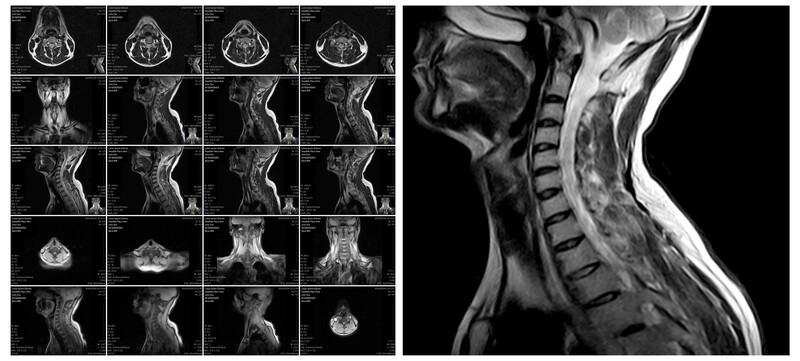

Everyday we get many emails. In many of these emails the person asking a question sends me their cervical neck MRI findings. That is all they send: A cut and paste of their MRI report. They never say what their pain is like, how this neck pain is affecting their day to day quality of life, or any other glimpses into how this chronic neck pain is hurting them.